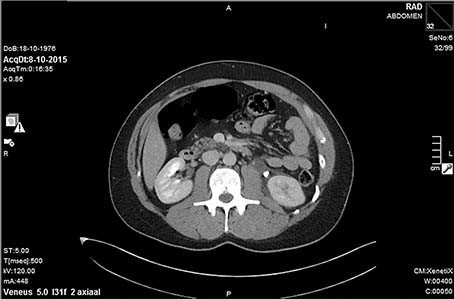

Na drie uur meldt patiënt zich wederom op de SEH. De buikpijn is heviger geworden, VAS 10. Het lichamelijk onderzoek toont nu diffuus drukpijn in abdomen met weliswaar enige défense musculaire, maar geen geprikkelde buik en geen slagpijn. De creatinine is nu 122, verder geen afwijkingen. De urine is schoon. De pijn breekt zelfs door tweemaal morfine 5 mg intraveneus en daarop wordt een spoed CT-abdomen met contrast gemaakt bij verdenking op mesenteriale ischemie, abdominale aortadissectie of appendicitis. De CT toont een obstruerende uretersteen links met blow-out van de linkernier en ureter met forse contrastlekkage [figuur 1 en figuur 2]. De uroloog neemt de patiënt gelijk op. Hij komt de nacht goed door met morfine 5 mg 6 dd en krijgt ’s morgens een dubbelloops J-katheter geplaatst.1 De patiënt gaat na 2 dagen in prima conditie naar huis. Meer dan 6 weken later wordt de J-katheter uiteindelijk verwijderd. De restfunctie van de nier lijkt volledig hersteld.